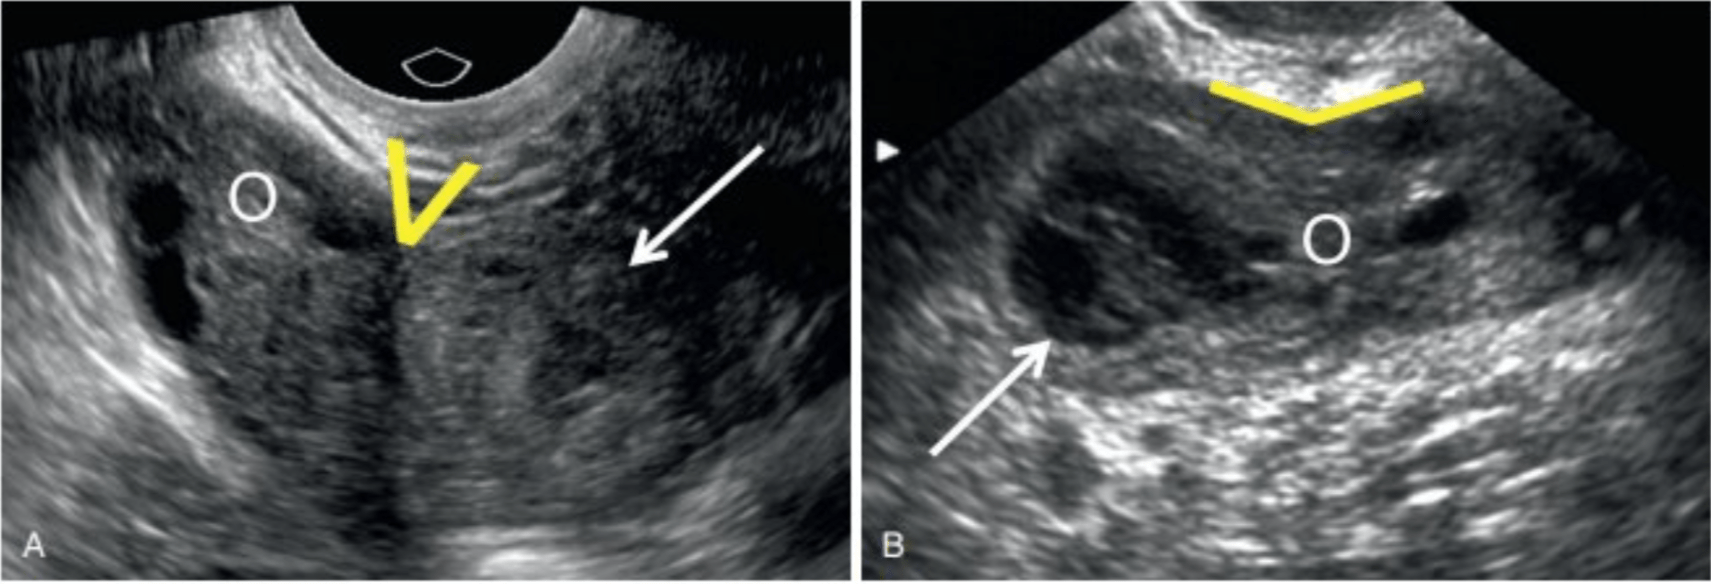

How do you differentiate cervical ectopic from incomplete abortion on US?

cervical ectopic - flow on doppler, negative sliding sign

incomplete abortion - no flow on doppler, positive sliding sign